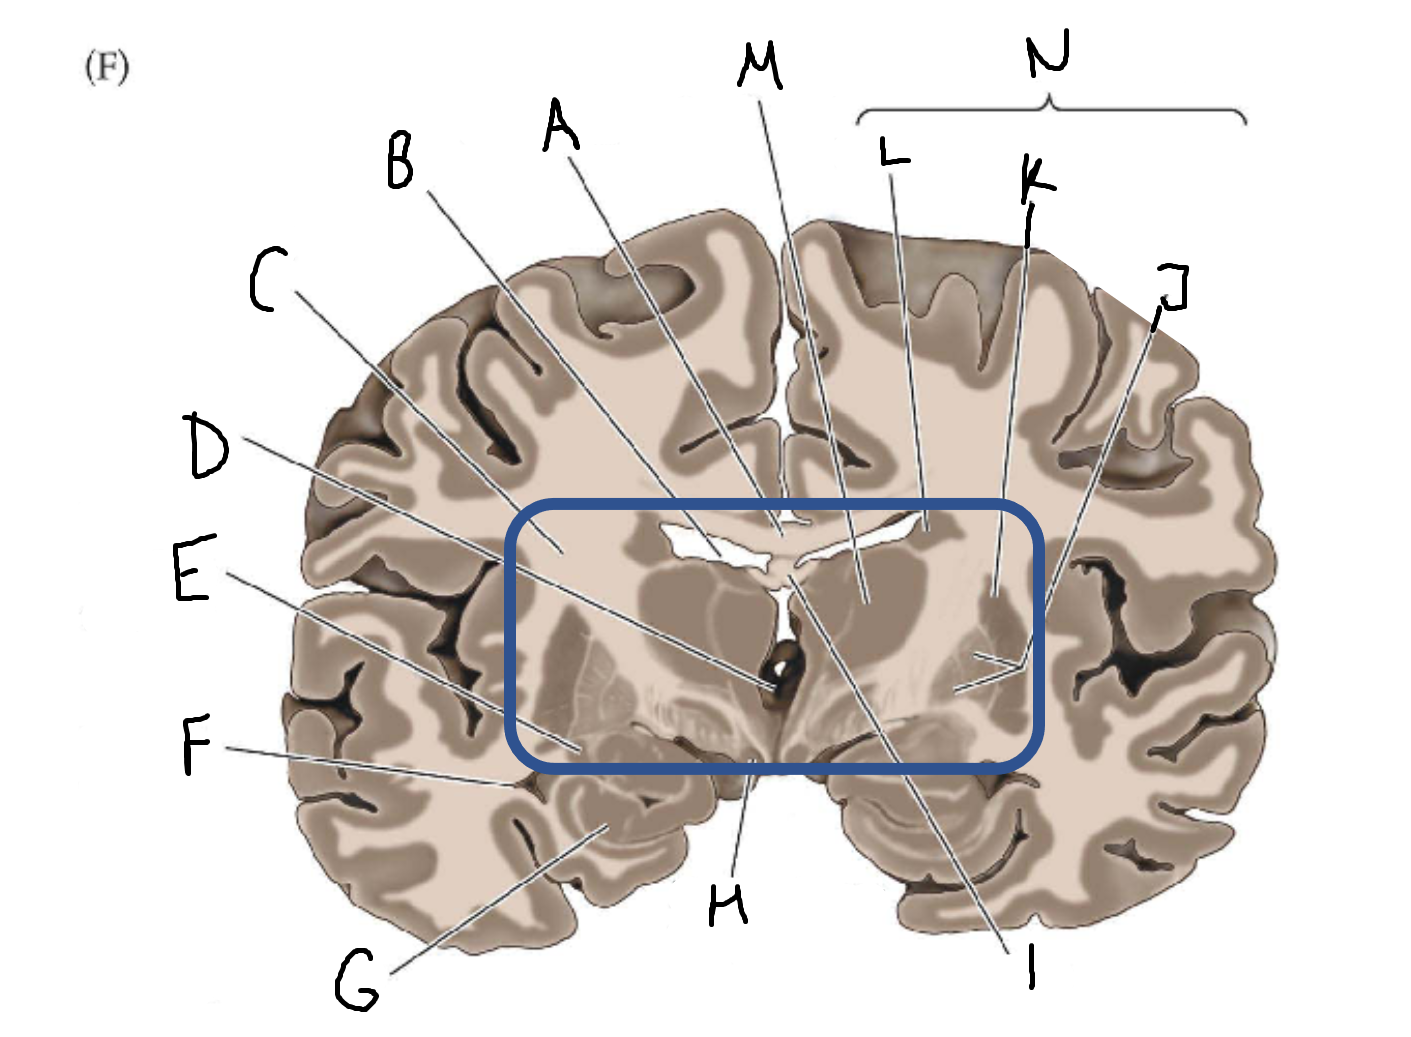

A

corpus callosum

B

lateral ventricle

C

internal capsule

D

third ventricle

E

tail of caudate nucleus

F

lateral ventricle

G

hippocampus

H

mammillary body

I

fornix

J

globus pallidus

K

putamen

L

caudate

M

thalamus

N

basal ganglia